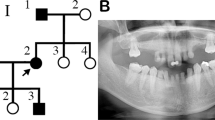

The first index patient was a boy born with a bilateral cleft lip, a left-sided cleft of the alveolus, and a complete cleft of the hard and soft palate. He had agenesis of 4 deciduous and 17 permanent teeth. Additional features were growth retardation, hypermetropia, and a small median alveolar cleft in the mandible ( Figure 1a – h ). His mother also had severe TA, but not OFC, as did the maternal grandmother and her brother.

Clinical photographs, orthopantomogram (OPT), image from cone beam computed tomogram (CBCT), and pedigree of index patient 1 (a–h) and index patient 2 (i–q). (a and b) Frontal and lateral facial photographs of index patient 1 at 12 years of age showing a repaired bilateral cleft lip with a left-sided cleft alveolus and a complete cleft of the anterior and posterior palate. He has a wide nasal base, full nasal tip, wide nasal bridge (h), and a dip in the chin (a and b). (c) His mother and maternal grandmother and her brother also have tooth agenesis (TA) but no other orofacial abnormalities. (d) The patient presented with severe TA or oligodontia; he had agenesis of four deciduous teeth (52, 62, 72, and 82) and was missing 18 teeth in the permanent dentition, 17 due to TA (teeth 15, 14, 13, 12, 22, 23, 24, 25, 35, 34, 33, 32, 31, 41, 42, 44, 45; excluding third molars) and 1 due to extraction (tooth 36). He had a small median mandibular cleft, which can be seen on the (d) orthopantomogram (OPT) at the green arrow, (f and g) the intraoral photographs, and (h) the horizontal tomographic view of a CBCT. (e) The OPT of the boy’s mother shows severe TA because she was missing 13 permanent teeth. (i and j) Frontal and lateral photographs of index patient 2 at 9 years of age showing mild facial dysmorphic features including a narrow nasal ridge, posteriorly rotated ears with a thin helix, small earlobes, and a long superior crus antihelix. (k) He has unaffected parents and two unaffected brothers. (l) The OPT shows TA of two deciduous teeth (52 and 62) and TA of nine permanent teeth (17, 15, 14, 12, 22, 25, 27, 35, and 45). (l and m) There is an ectopic tooth germ in the upper right molar area (tooth 17 or 18) and a horizontally impacted premolar germ (tooth 24) in the left upper quadrant. (n) The occlusal photograph of the mandibular dental arch in the mixed dentition shows malposition of tooth 32. (o) The shapes of the palatal cusps of teeth 16 and 26 are abnormal, making them resemble a second molar on the occlusal photograph of the maxillary dental arch. (p and q) Clinodactyly of the fifth fingers. DT, deciduous teeth; PT, permanent teeth; OFC, orofacial clefting; STHAG, selective tooth agenesis.